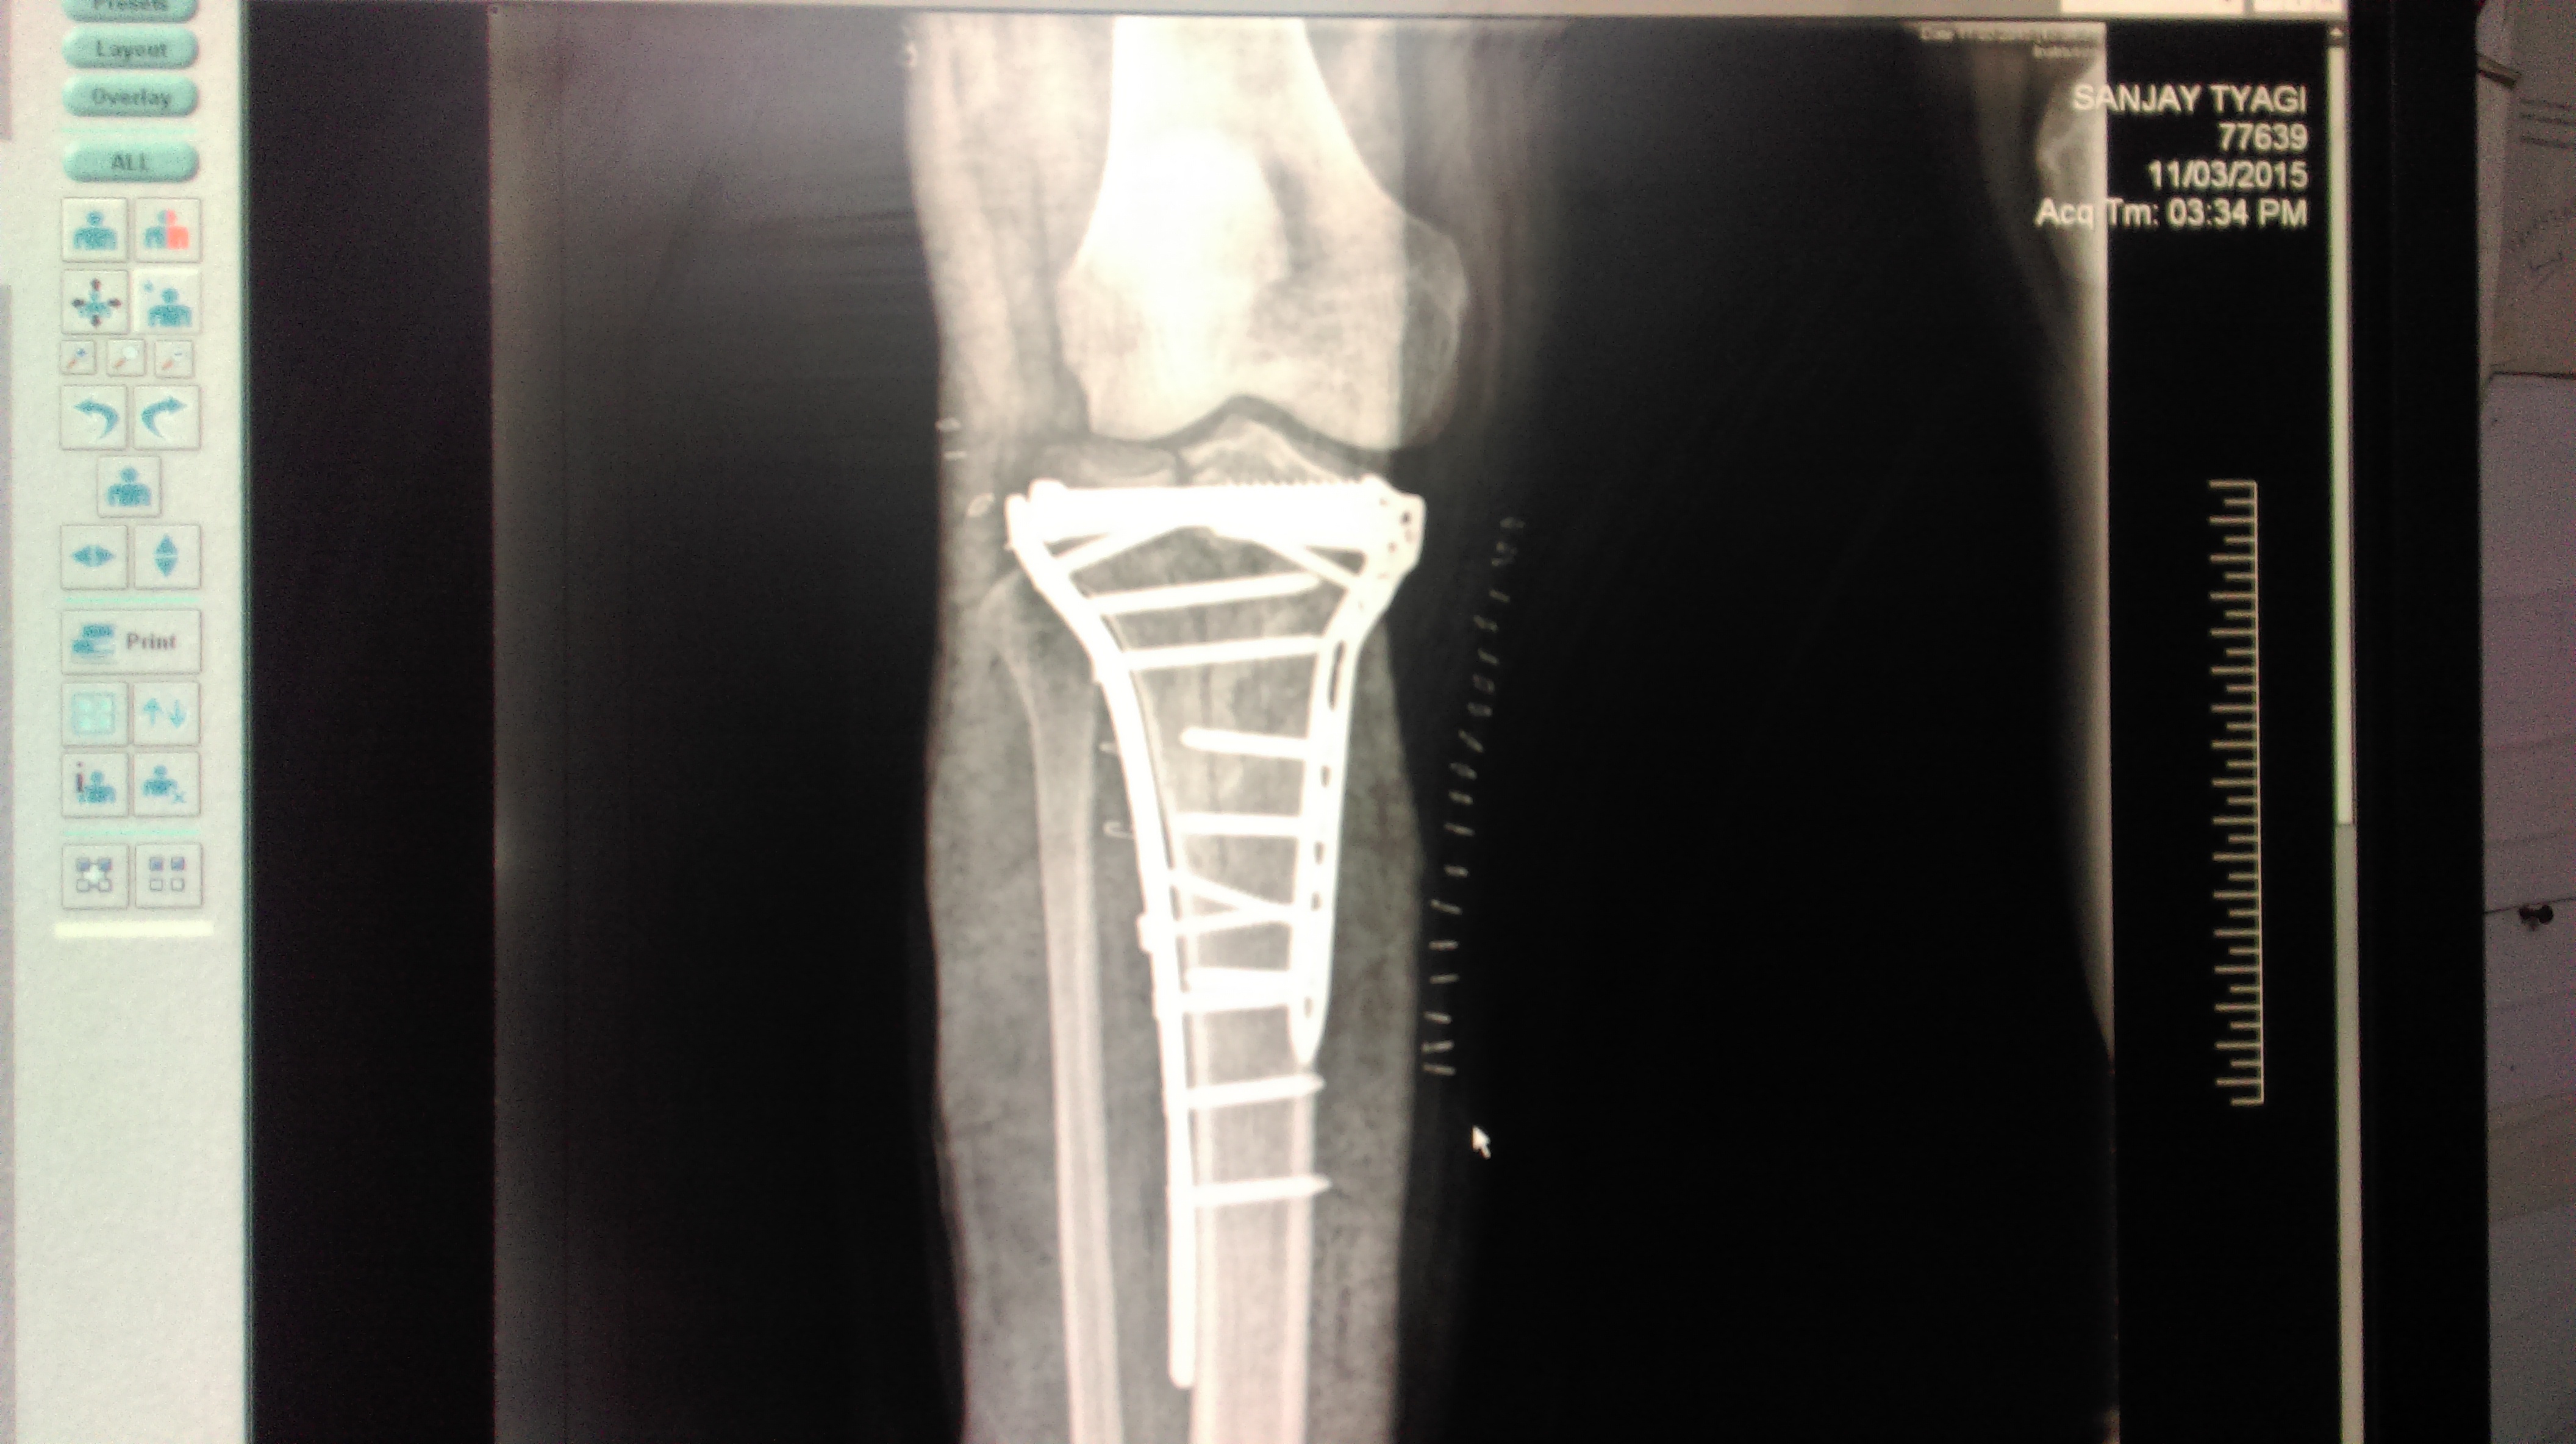

Total Knee replacement is a surgical procedure in which parts of an arthritic or damaged joint are removed and replaced with a metal, plastic, or ceramic device called a prosthesis. The prosthesis is designed to replicate the movement of a normal, healthy joint.

During the surgery, the damaged cartilage and bone is removed from your joint and replaced with prosthetic components made of metal, plastic, or ceramic. The prosthesis mimics the shape and movement of a natural joint.